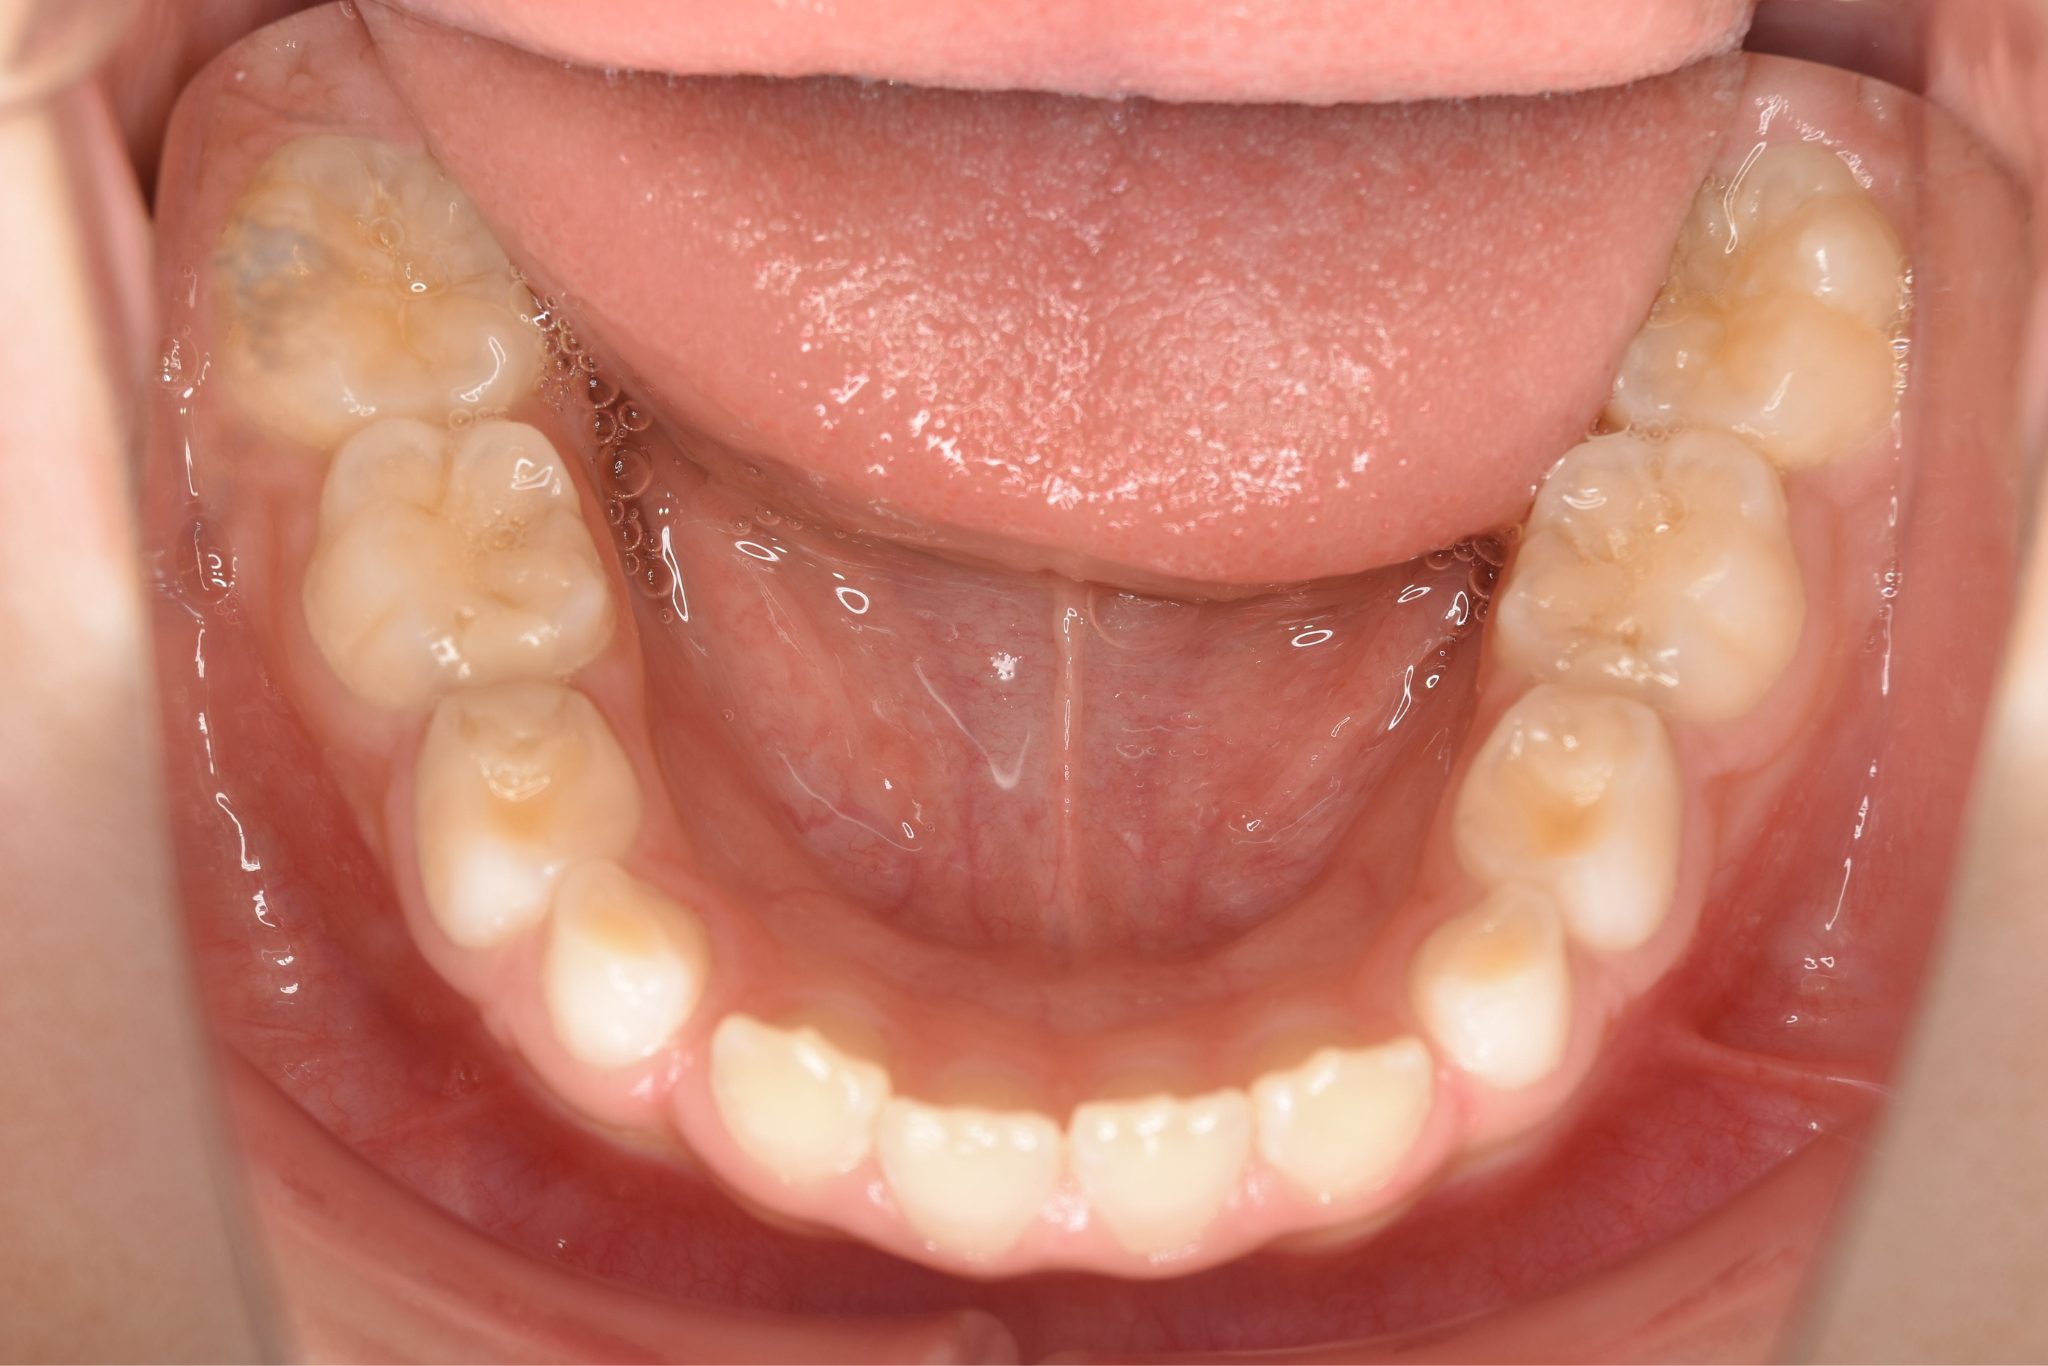

ビフォー

全顎ワイヤー矯正 症例_108

主訴 受け口|前歯がかみ合わない|顔貌

施術内容 小児矯正1期治療

治癒期間 3年11ヶ月間

費用 498,960円(税込)